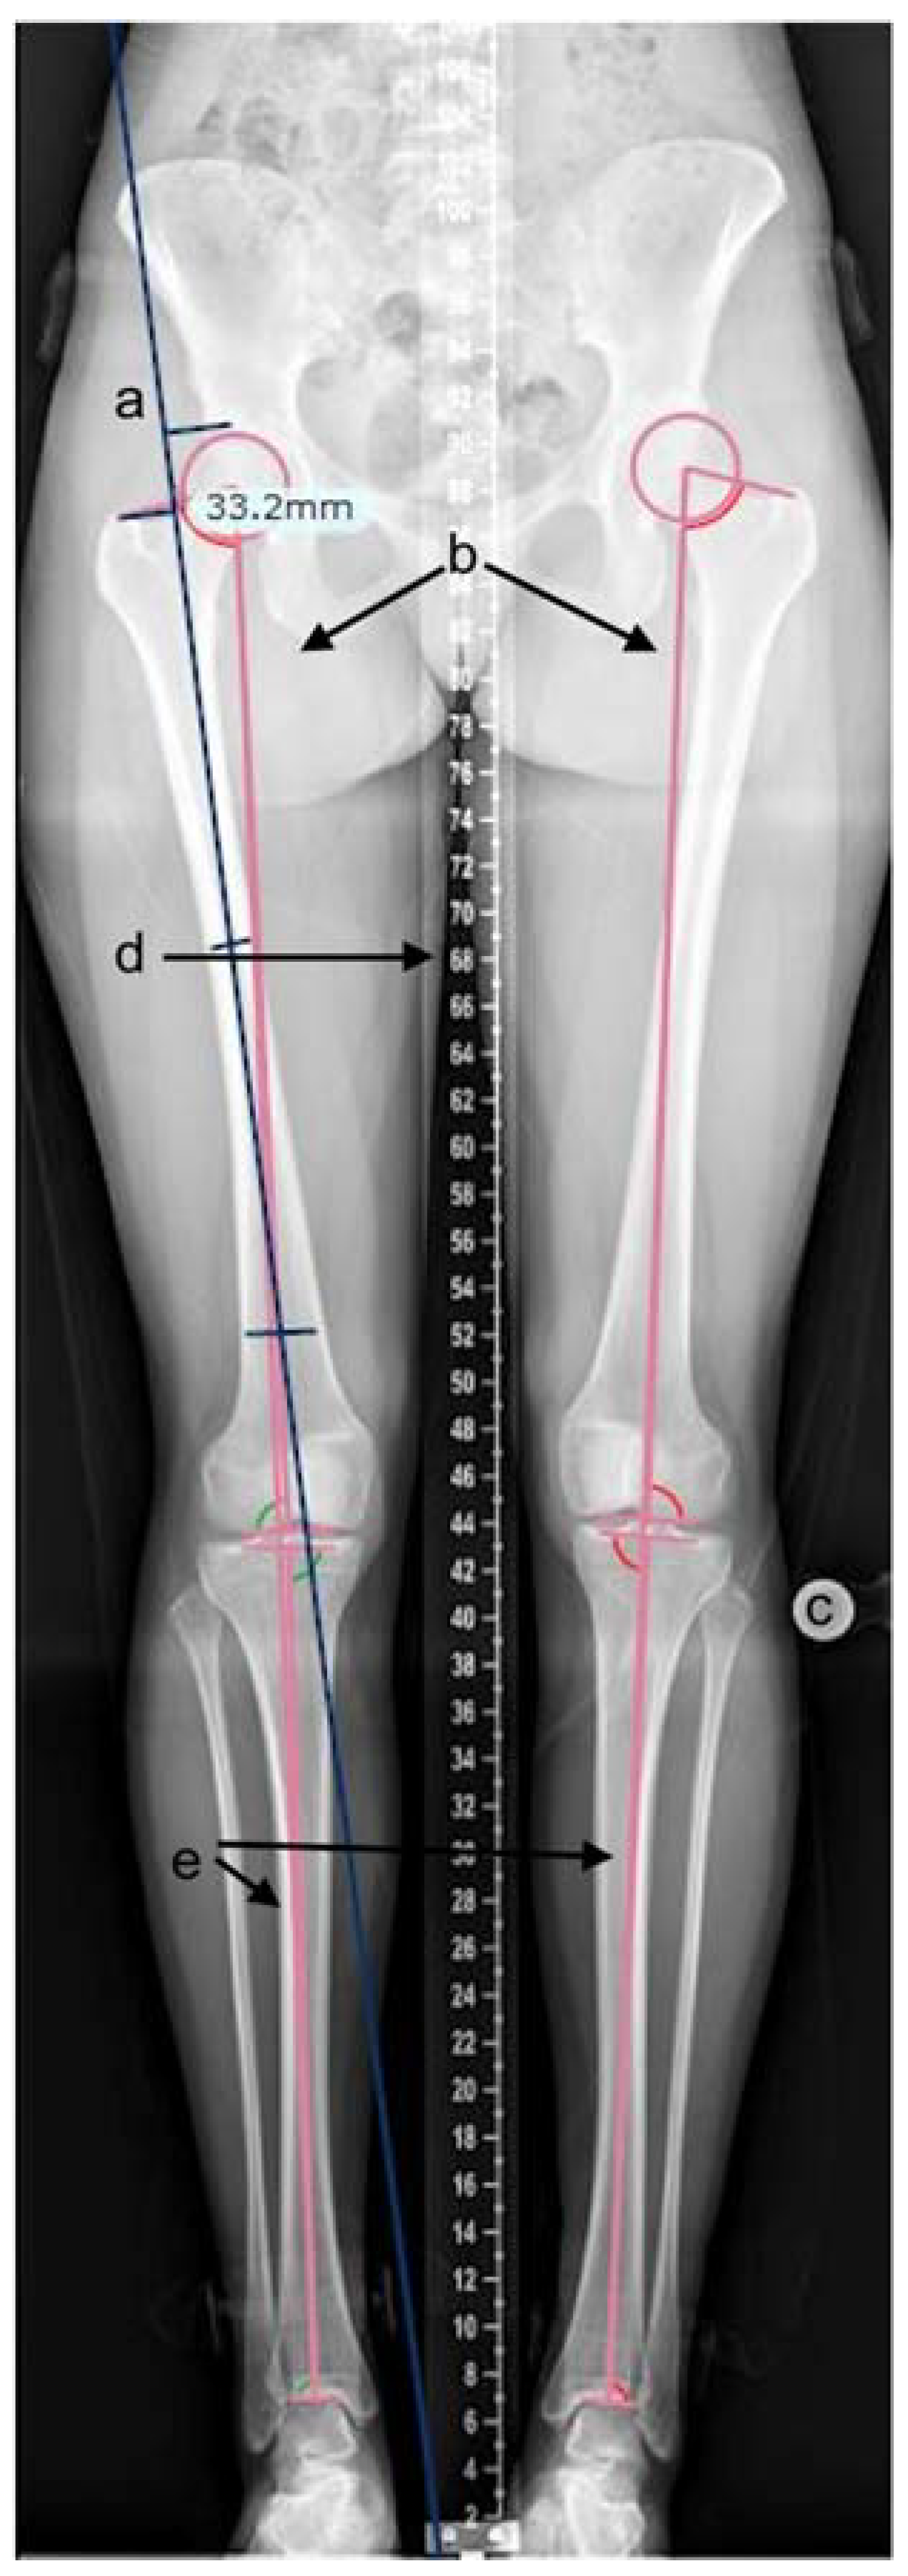

Radiographic measurements were performed on the calibrated, standardised long-leg standing radiographs. Adequate radiographs were defined as patellae positioned forward; bony landmarks were visible with the presence of a templating ball or scale measure. All measurements were performed using TraumaCad (Brainlab, Petach-Tikva, Israel) software (see Figure 1) [25]. Measurements included the articulo-trochanteric distance (ATD), femoral length, and tibial length. Measurements were performed using measurement tools in the software. ATD was measured by placing markers on the tip of the greater trochanter and superior aspect of the femoral head on a line oriented along the axis of the femur (Figure 1a). Femoral and tibial lengths were calculated by the software after the appropriate identification of bony landmarks by the investigator (Figure 1b,e). Proximal femoral growth disturbance was classified according to Kalamchi–MacEwen [26] for a grade of avascular necrosis. All three authors independently reviewed the measurements, and discrepancies were resolved with consensus [27].

Figure 1.

TraumaCad measurement of leg length parameters. (a) tool for articulo-trochanteric distance, (b) femoral length tool, (c) templating ball for calibration, (d) measuring ruler, (e) tibial length tool.